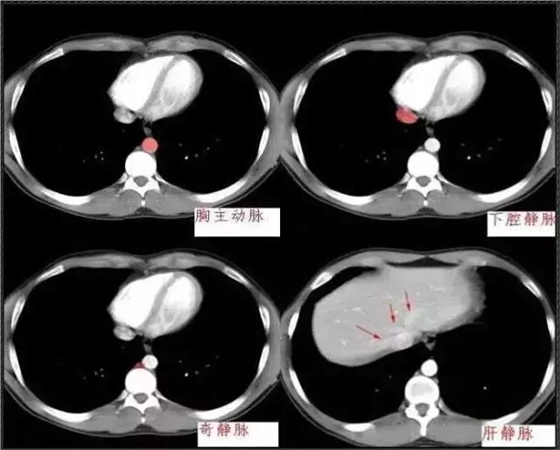

640.webp (1).jpg